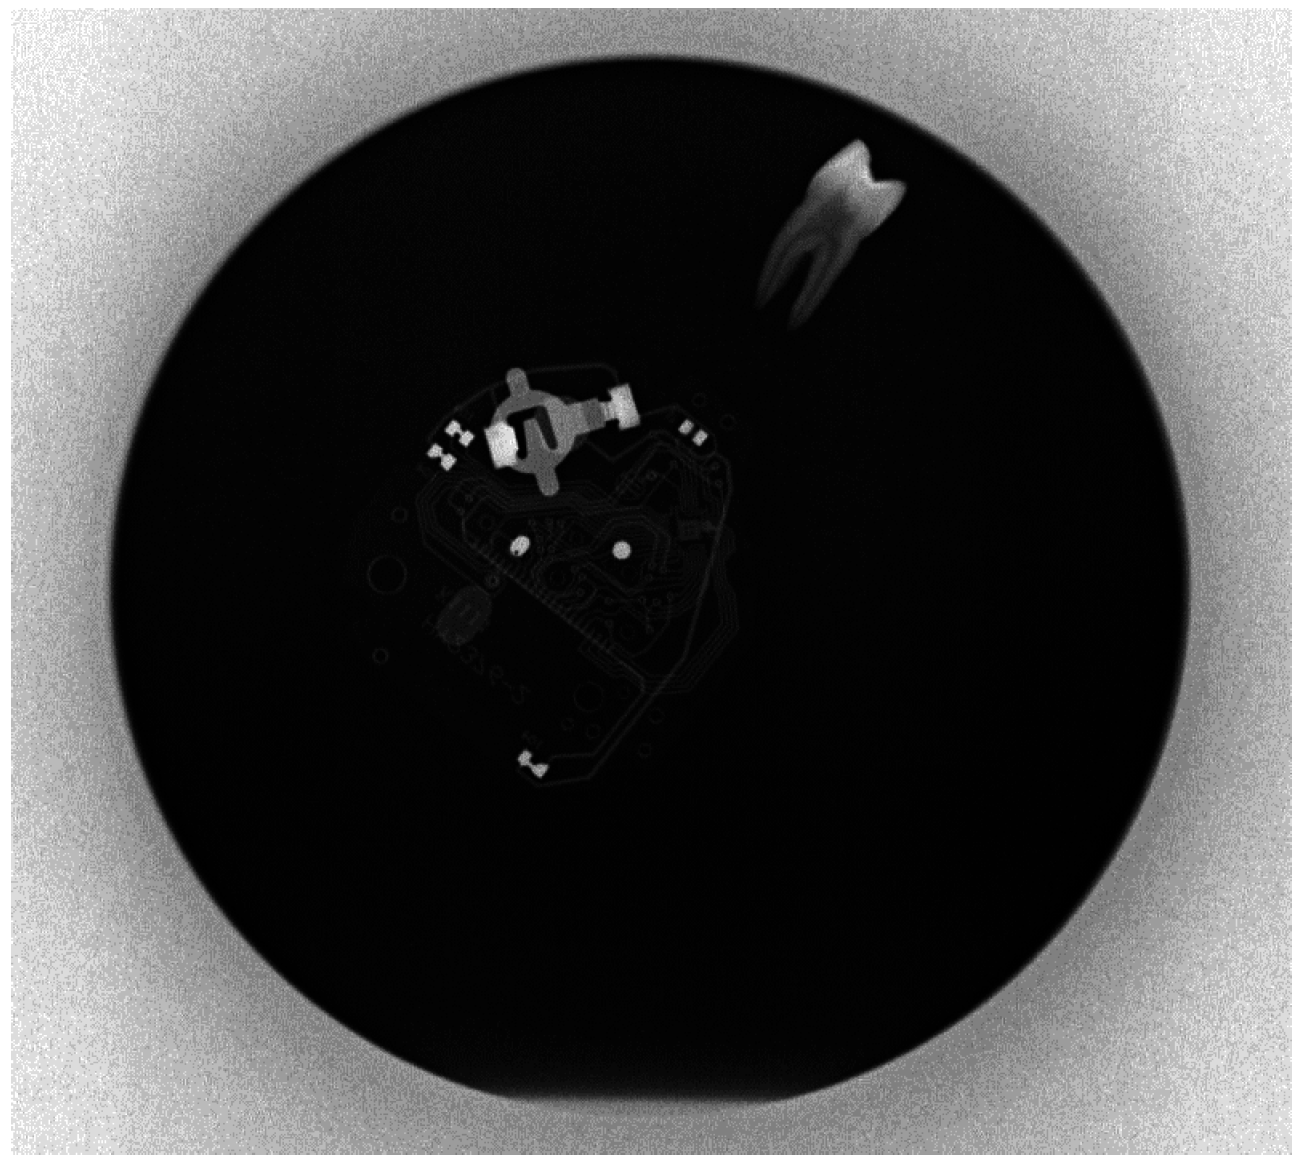

3.3. Test of X-Ray Tube